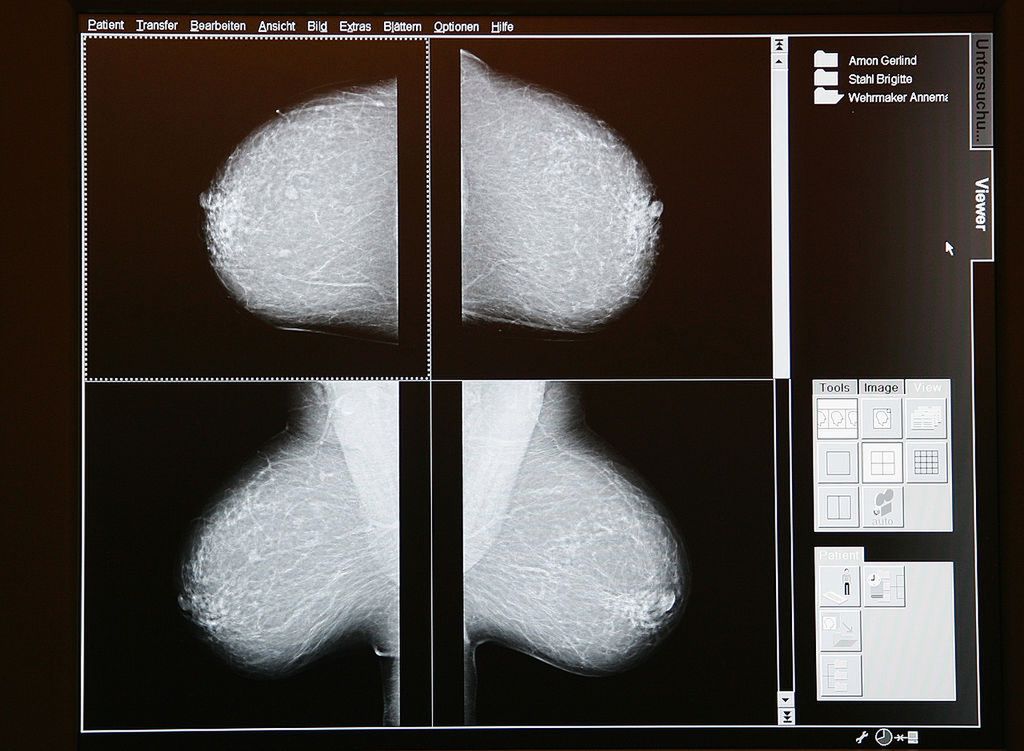

© Obraz badania mammografem/Getty Images

Najwięcej miejsca autorka poświęca kwestii wpływu współczesnego świata na zachorowalność na nowotwory: raka piersi czy sutka. Jak się okazuje, istnieje korelacja pomiędzy wczesnym dojrzewaniem płciowym (coraz wcześniejszym wraz z kolejnymi latami) i zachorowalnością na choroby nowotworowe.

"W 2007 roku Fundusz Raka Piersi opublikował raport, z którego wynikało, że opóźnienie pokwitania dziewczynek tylko o jeden rok oznaczałoby tysiące przypadków raka sutka mniej. (...) Pierwsza miesiączka przed 12. rokiem życia oznacza, że ryzyko pojawienia się nowotworu jest o połowę wyższe niż w przypadku pierwszej menstruacji w wieku 16 lat". Dlaczego tak jest? "Jedna z teorii mówi, że dojrzewanie - kiedy komórki naszego ciała są bardzo niestabilne - szczególnie uwrażliwia piersi na kancerogeny. A jeśli zaczyna się ono wcześniej, to ten wrażliwy okres jest dłuższy". Według badań, największy wpływ na przedwczesne, dużo wcześniejsze niż kiedyś dojrzewanie, mają otaczające nas chemikalia i związki chemiczne zaburzające równowagę hormonalną.